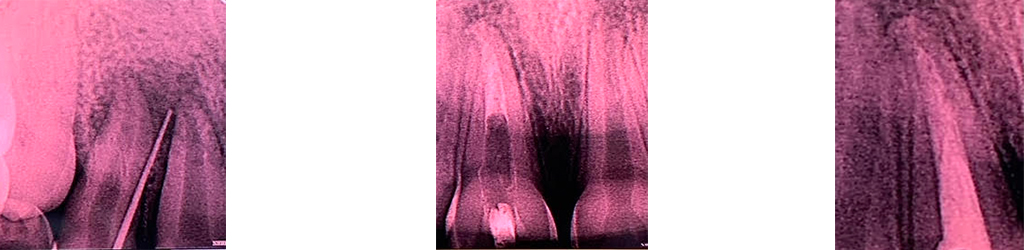

A 10 year old girl reported to the clinic with the complaint of swelling and pain of anterior right upper region. The IOPA x-ray evaluation revealed periaical lesion. Treatment started with root canal treatment of the affected tooth. After access preparation using endo z bur, repeated canal irrigation was done using sodium hypochlorite 3%. After completing biomechanical preparation with protaper gold repeated dressings were done using metapex and tri antibiotic paste. After waiting for few months the root canal filling was done using latest filling material MTA, MTA, present in the composition of MTA Fillapex, is more stable than calcium hydroxide, providing constant release of calcium ions for the tissues and maintaining a pH which elicits antibacterial effects. The tissue recovery and the lack of inflammatory response are optimized by the use of MTA. Thus, MTA Fillapex is considered a great material for root canal treatment, considering its bioactive potential.

THIS BIOACTIVE MATERIAL HELPED US ACHIEVE GREAT RESULTS IN TERMS OF HEALING AND FUNCTIONALITY.